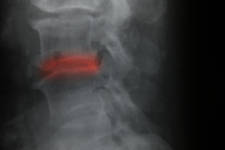

Leer másOLIF. Técnica minimamente invasiva para realizar fusiones vertebrales.

Última actualización el 23 octubre 2023 a las 07:07...